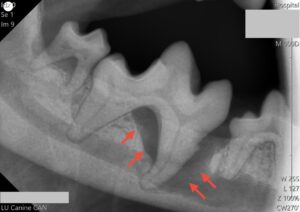

別症例(歯科レントゲンでの比較)

重度歯周病

この病気は進行すると細菌感染により歯根のまわりから骨を溶かしていきます。重度になると細菌により産生された膿が出口を求めてトンネルをつくり、歯肉をはじめとした口腔粘膜に穴をあけてしまう内歯瘻や、目の下や顎の下の皮膚に穴をあけてしまう外歯瘻、鼻と口の間に穴をあけてしまう口腔鼻腔瘻、場合によっては下顎骨の骨折を引き起こすことがあります。さらに、歯垢中の細菌が全身の血液中に流れ、心臓や腎臓、肝臓などの病気を引き起こすこともあります。

プロービングを行い、歯周ポケットの有無を確認した後、歯科専用のレントゲンを用いて歯周組織の状態を確認し、必要に応じて抜歯処置もしくはルートプレーニングやキュレッタージにより保存治療を行います。